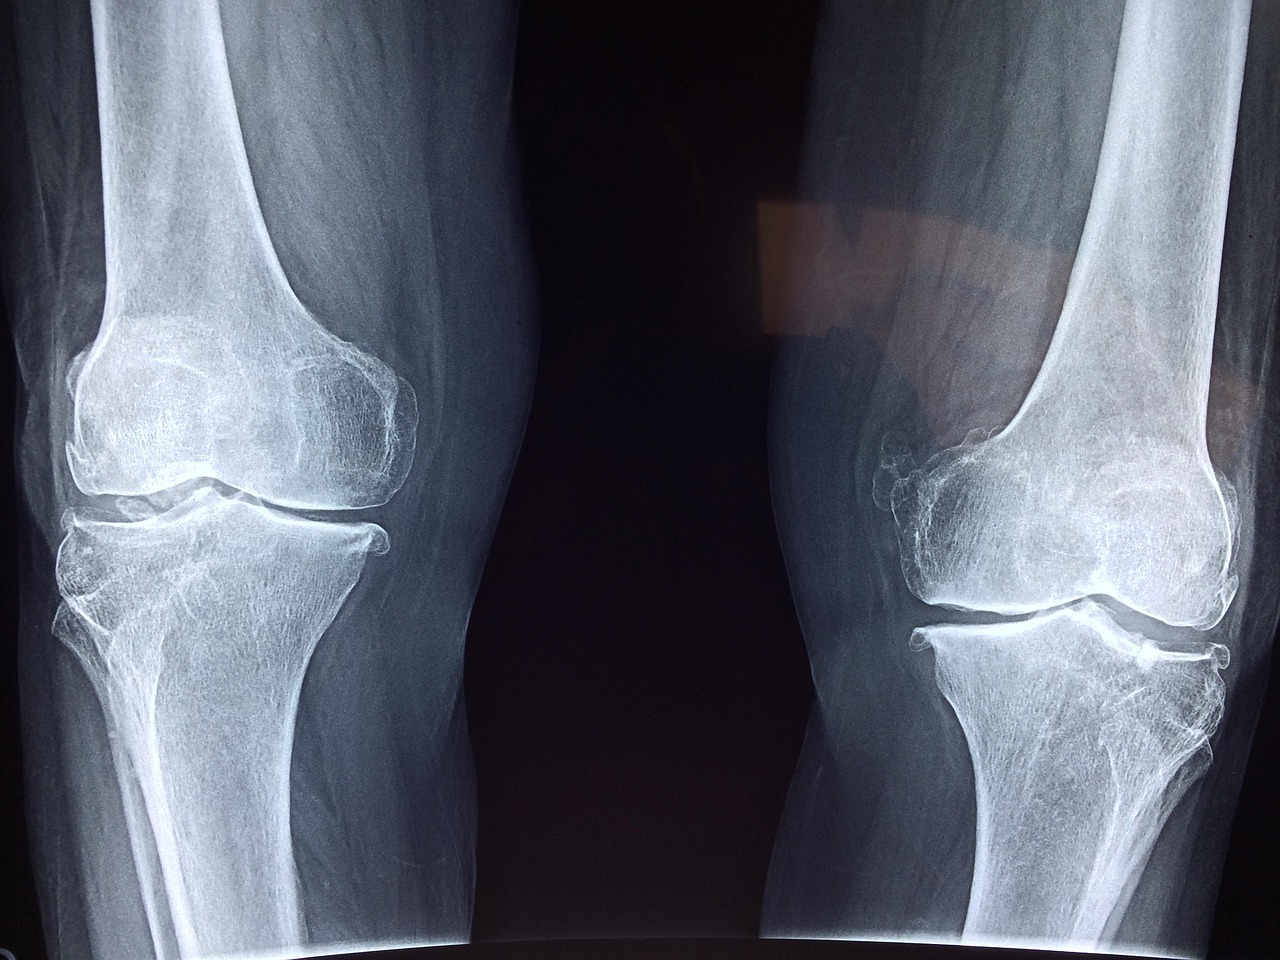

나이가 들면서 뼈의 밀도는 점차 감소하게 되며, 이는 골다공증과 같은 만성 질환으로 이어져 삶의 질을 심각하게 저해할 수 있습니다. 특히 골다공증은 우리 어르신들의 건강한 백세 시대를 위협하는 가장 무서운 질환 중 하나로 꼽힙니다. 뼈가 약해지면 작은 충격에도 골다공증성 골절이 발생할 수 있으며, 이는 심한 통증은 물론 움직임의 제한으로 이어져 독립적인 생활을 어렵게 만들기도 합니다.

골다공증은 뼈의 강도가 약해져 작은 충격에도 쉽게 골절될 수 있는 질환입니다. 마치 스펀지처럼 뼈 안에 구멍이 많이 생겨 뼈의 밀도가 낮아지는 것인데요. 뼈가 약해지면 낙상 시 척추, 고관절, 손목 등에 골절이 발생하기 쉽습니다. 특히 고관절 골절은 거동 불편과 사망률 증가로 이어질 수 있어 더욱 위험합니다. 골다공증으로 인한 골절은 심한 통증을 유발하고 장기간의 치료와 재활을 필요로 하며, 이는 신체적 고통뿐만 아니라 심리적 위축과 사회생활 단절로까지 이어질 수 있습니다.

뼈 건강에 대한 관심과 노력에도 불구하고, 골다공증은 누구에게나 발생할 수 있는 질환입니다. 특히 폐경 이후 여성이나 노년층은 골다공증 발생 위험이 높으므로, 정기적인 골밀도 검사를 통해 자신의 뼈 상태를 확인하는 것이 매우 중요합니다.